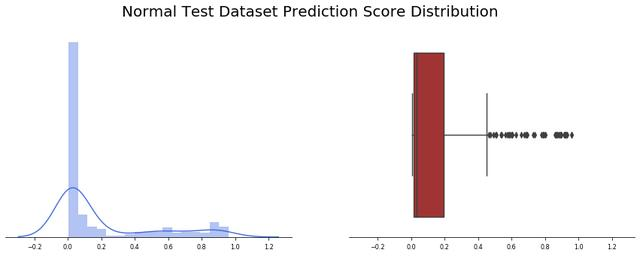

用正常(健康)患者的图像进行测试

由于输入数据集也有正常患者(未经训练)的X光图像,让我们应用模型2(Covid/普通肺炎)看看结果如何

在这种情况下,结果并没有模型1测试中看到的那么糟糕,在234幅图像中,有45幅出现了假阳性(19%)。

好吧,理想情况是对每种情况使用正确的模型,但是如果只使用一种,那么模型2是正确的选择。